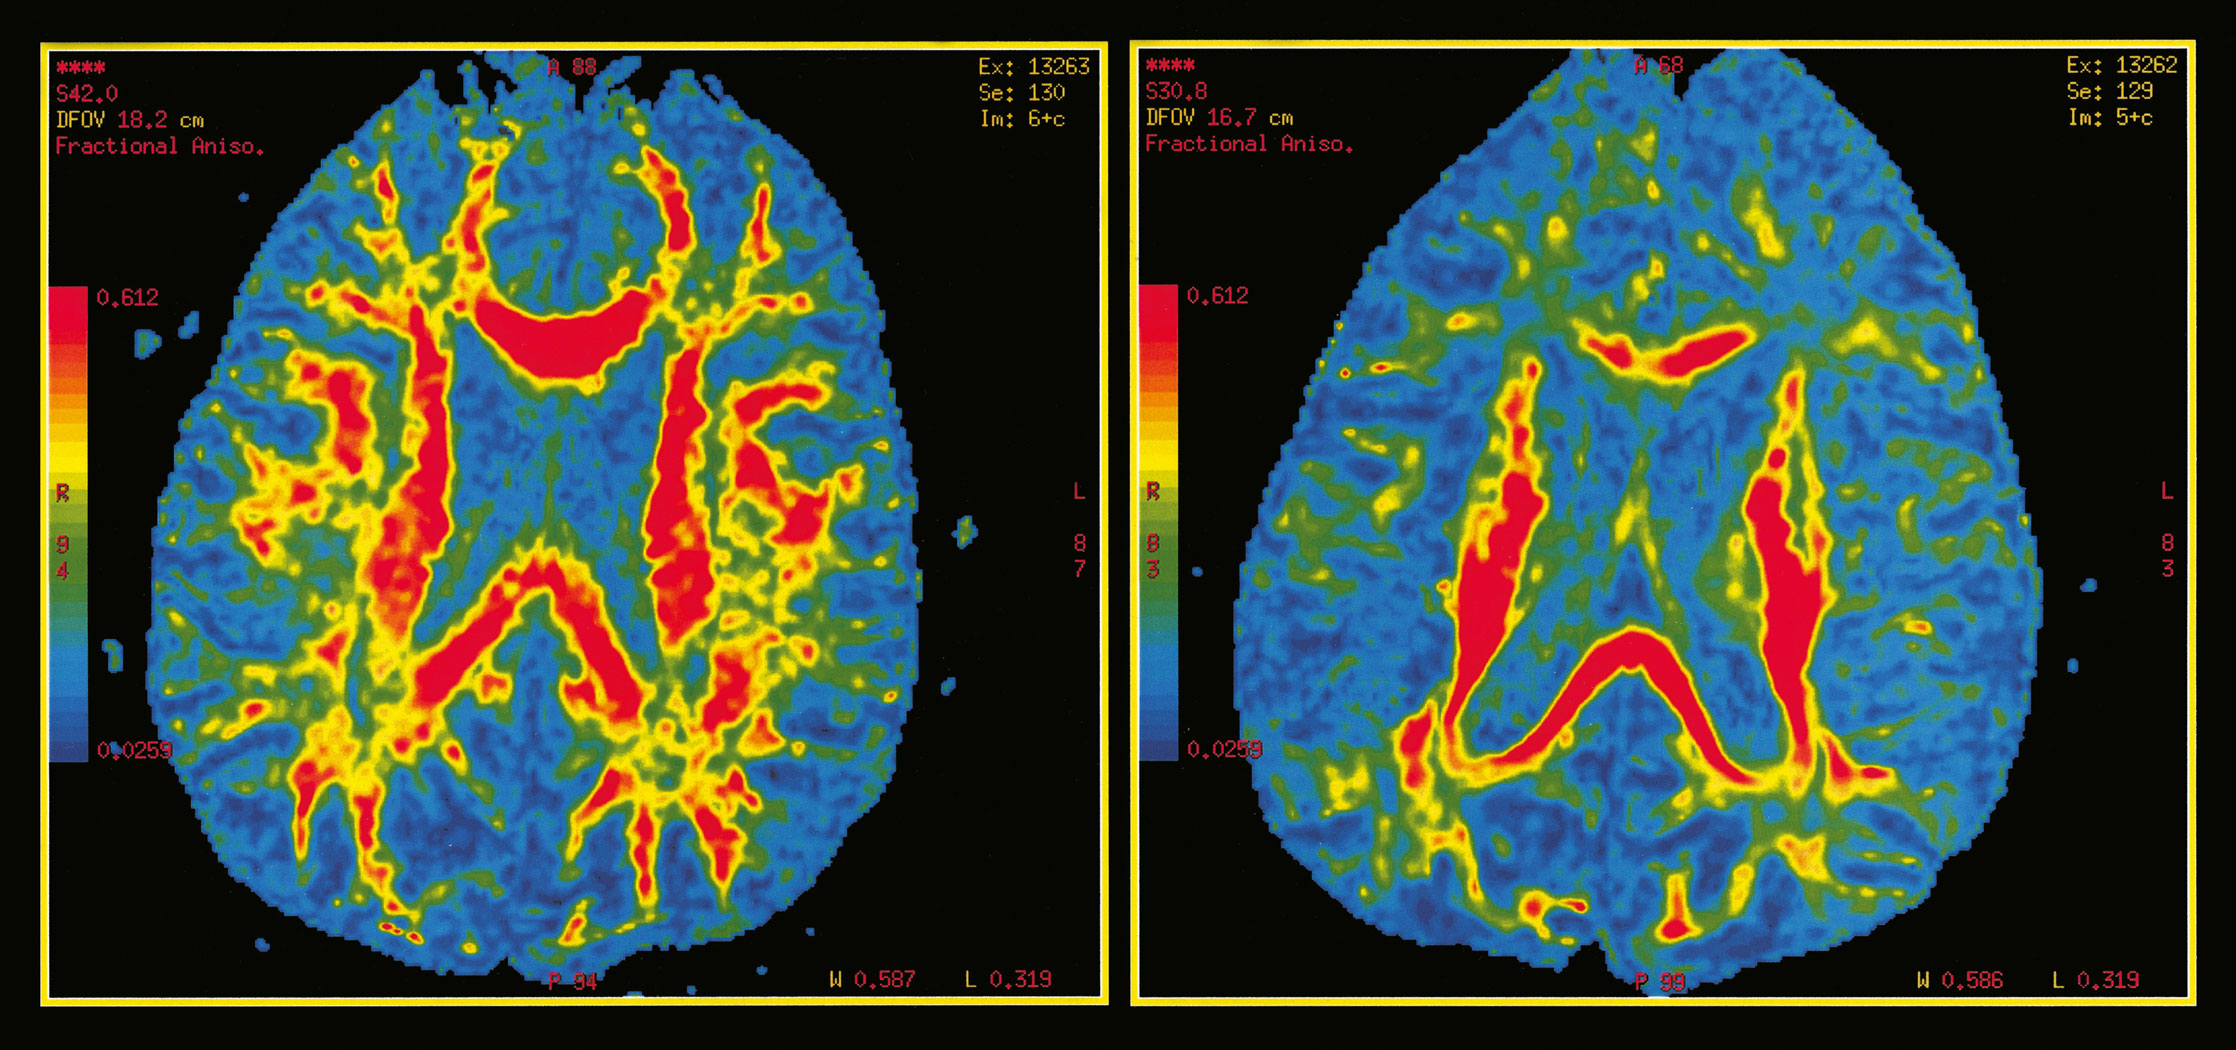

Przykładowe przekroje mózgu uzyskane dzięki rezonansowi magnetycznemu (MRI). Porównanie aktywności mózgu (kolor czerwony) u osoby zdrowej (z lewej) i pacjenta z rozpoznanym alzheimerem. Przykładowe przekroje mózgu uzyskane dzięki rezonansowi magnetycznemu (MRI). Porównanie aktywności mózgu (kolor czerwony) u osoby zdrowej (z lewej) i pacjenta z rozpoznanym alzheimerem. Universal Images Group / Getty Images